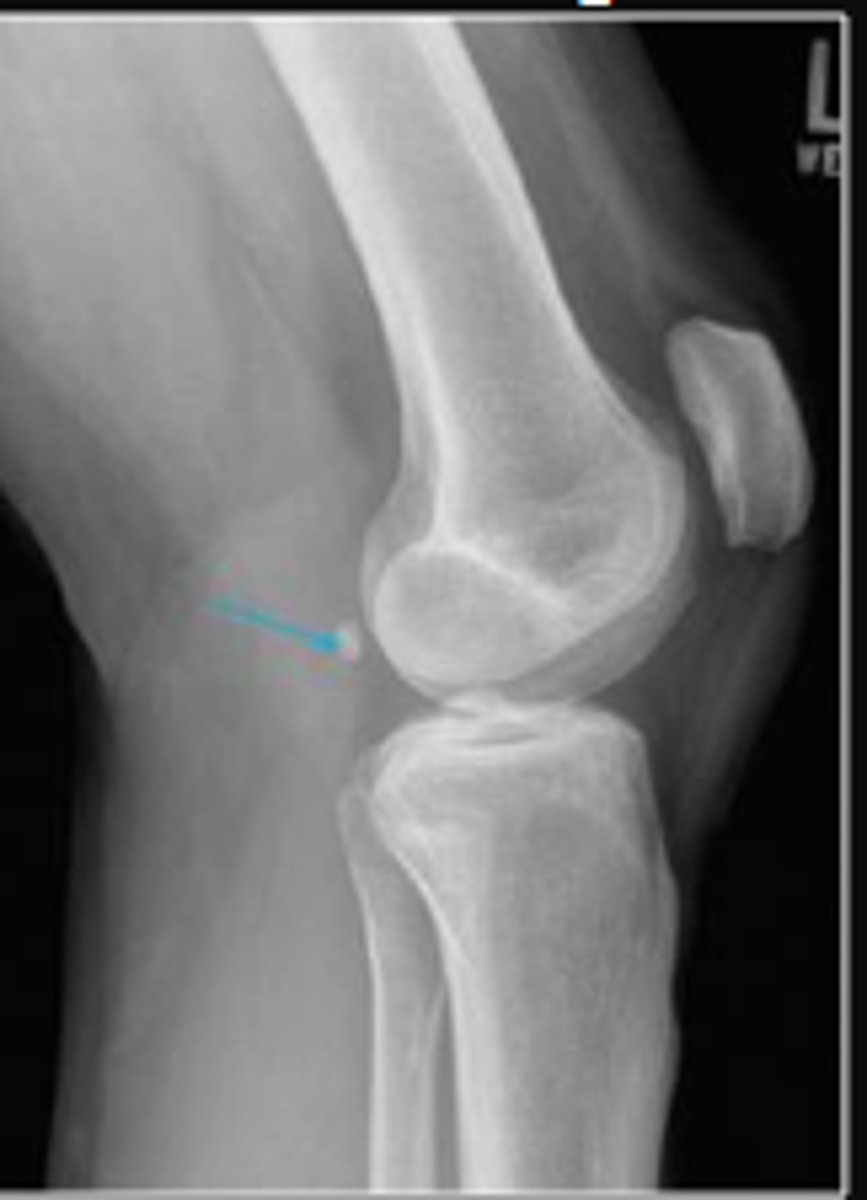

Right lateral knee

What is the name of the radiographic view?